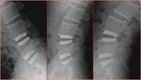

The LaserCUSING additive laser melting method combines the strengths – and eliminates the weaknesses – of traditional titanium or PEEK components for spine cage applications. A laser-melted component can now offer the biocompatibility of titanium with the desired elasticity of a plastic material in a single product. Laser-melted spine cages have a very complicate geometry and not require to be re-treated (images 1a, b and c) to ensure an optimal surface structure. The highlight of this solution: its geometry, with partially different density distributions (embedded web-like structures), now gives titanium parts the same elasticity as a PEEK solution. Laser-melted cages can also be affordably manufactured in various dimensions depending on the anatomy of the patient, allowing for customised manufacturing. According to CEO Stefano Caselli, laser-melted cages represent "a true innovation that combines material-specific advantages such as biocompatibility, i.e., the ability to embed the material into the bone structure, and elasticity that is customised for the human body in a single product" (image 2). Surgeons can easily locate the cages using CT or MRI imaging. Laser melting also allows custom or small-series manufacturing, including "made-to-order" cages for patients with special anatomical conditions or standard solutions for other patients. A clinical study conducted in March 2014 in cooperation with Carl von Ossietzky University in Oldenburg, Germany, confirmed an excellent healing prognosis with these implants. (*Oldenburg study)